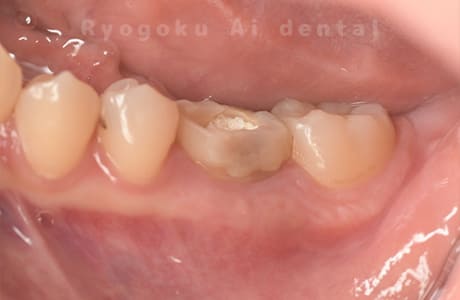

歯が欠けたとのことでご来院された患者様です。神経まで虫歯が及んでいたため、神経を除去し、治療を行いました。経過良好です。

<リスク・副作用>

術後は痛み、腫れ、痺れなどの副作用が生じる場合があります。症状が再発する可能性があります。